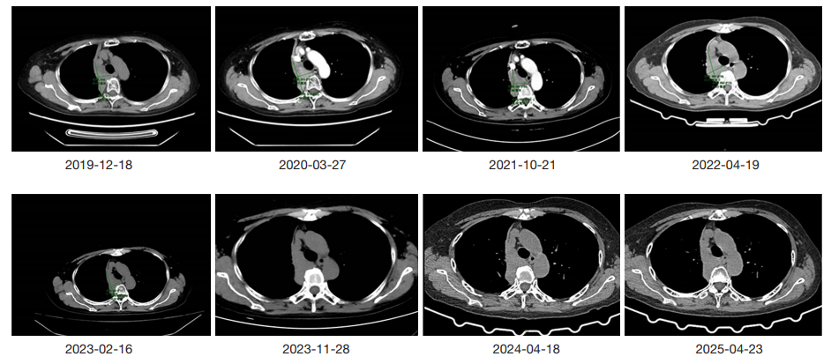

2015  10 月,患者因 “咳嗽、咳白痰” 就医,12 月胸部 CT 发现右肺上叶肿块和纵隔淋巴结肿大,最终确诊为IIIB 期肺腺癌(T4N2M0) 。通过下一代测序(NGS)检测,医生发现她携带EGFR 19 号外显子缺失突变(这是 EGFR 靶向药的敏感突变),随即启动一线治疗:吉非替尼(250mg / 天,第一代 EGFR-TKI)。治疗 2 周期后,CT评估显示肿瘤明显缩小,达到部分缓解(PR),疗效显著。

第一代 EGFR-TKI 吉非替尼治疗期间的胸部 CT 图像。(AC)在开始使用 EGFR-TKI 之前的心肺 CT 检查结果。(BD)开始使用吉非替尼后的心肺 CT 检查结果。红色圆圈代表肺部肿瘤病灶。